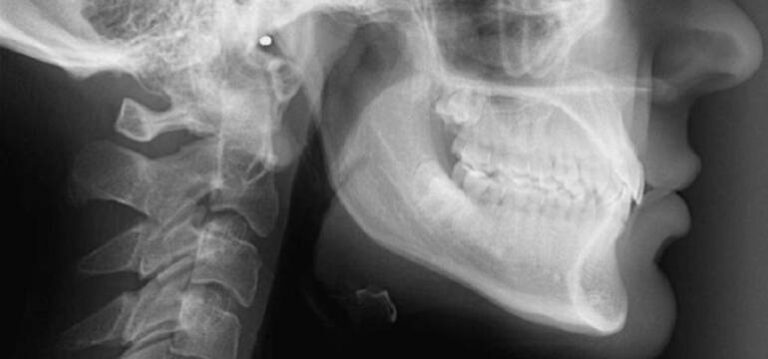

Definicja i znaczenie Aparat retencyjny to specjalistyczne urządzenie stomatologiczne, które stosuje się po zakończeniu leczenia ortodontycznego, ponieważ jego głównym zadaniem jest nie tylko utrzymanie prawidłowego ustawienia zębów, ale także zapobieganie nawrotowi wady zgryzu. W klinice stomatologicznej ortodonta Wrocław dobiera odpowiedni…